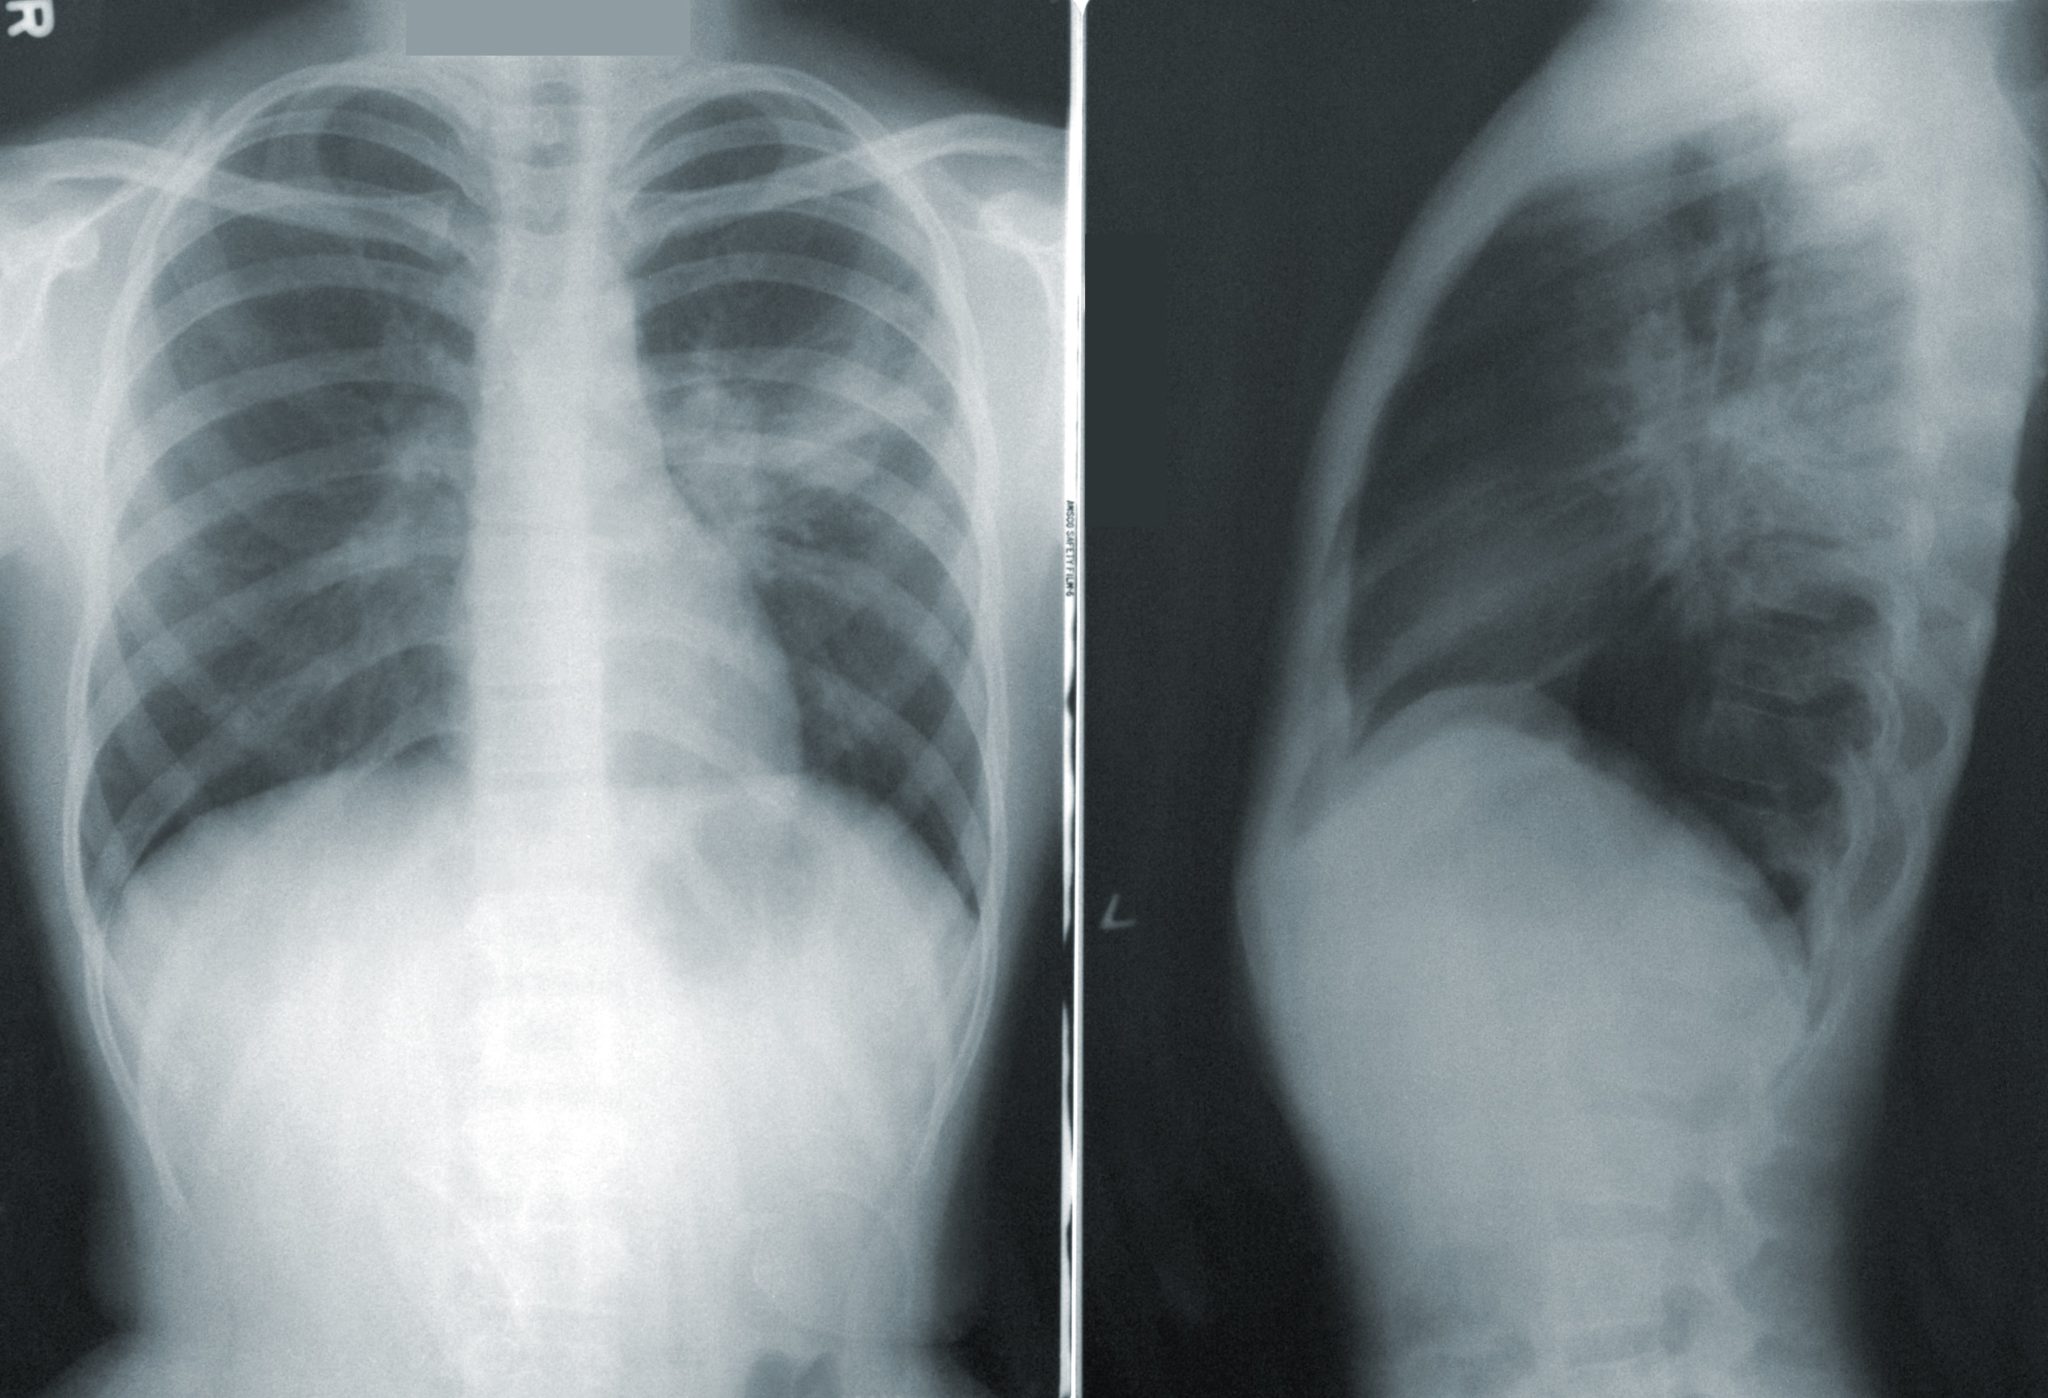

Ο καρκίνος του πνεύμονα εξακολουθεί να αποτελεί κύρια αιτία θανάτων από καρκίνο τόσο σε παγκόσμιο επίπεδο όσο και στην Ταϊβάν. Για την καταπολέμηση του καρκίνου του πνεύμονα και τη βελτίωση των ποσοστών επιβίωσης, η Ταϊβάν δημιούργησε το Εθνικό Πρόγραμμα Έγκαιρης Ανίχνευσης του Καρκίνου του Πνεύμονα, που αποσκοπεί στην έγκαιρη ανίχνευση της ασθένειας, μέσω της διαγνωστικής εξέτασης με αξονική τομογραφία χαμηλής δόσης (LDCT).

Η έγκαιρη ανίχνευση είναι ζωτικής σημασίας για τη βελτίωση των αποτελεσμάτων του καρκίνου του πνεύμονα και ο έλεγχος αυτός έχει αποδειχθεί αποτελεσματικός στη μείωση των ποσοστών θνησιμότητας. Ωστόσο, τα υφιστάμενα κριτήρια ελέγχου στις ΗΠΑ και άλλες χώρες περιορίζουν την επιλεξιμότητα μόνο στους βαρείς καπνιστές, αφήνοντας μια σημαντική μερίδα του πληθυσμού σε κίνδυνο.

Τα προκαταρκτικά αποτελέσματα από τον ένα χρόνο λειτουργίας του προγράμματος ήταν ελπιδοφόρα. Συνολικά εξετάστηκαν σχεδόν 50.000 άτομα, από τα οποία τα 4.406 έλαβαν θετικό αποτέλεσμα ελέγχου και τα 531 διαγνώστηκαν τελικά με καρκίνο του πνεύμονα. Αξιοσημείωτο είναι το γεγονός ότι το 85% των περιπτώσεων καρκίνου του πνεύμονα διαγνώστηκε σε πρώιμο στάδιο (στάδιο μηδέν ή ένα).